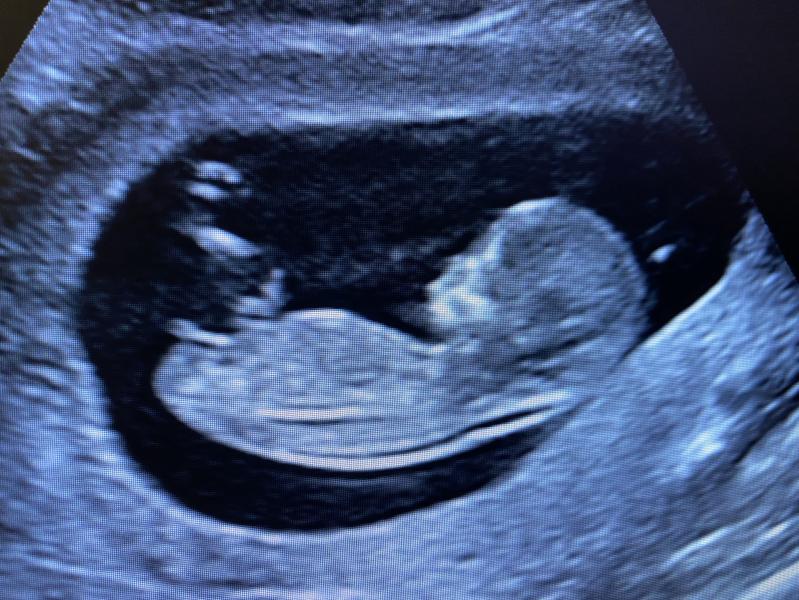

Страшное дело эти ваши УЗИ…

Шансов не прослезиться просто нет😑

Еще доктор такая милая в 4м роддоме, умиляется, бусинкой называет (не пойму только меня или ребенка🤭)

Хах. Посмотрела фотку и первая мысль «ого, 12я неделька а уже какой пацан». Следующая мысль «а че именно пацан?». Интересно, угадала ли)

Очень похоже, что у Вас девочка)))

@depilmood у вас очень хороший аппарат узи был и ракурс )) как по мне, то там прям 100% девочку видно уже))